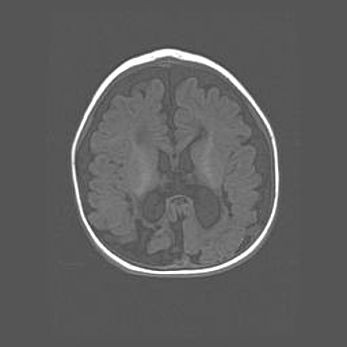

Открытая гидроцефалия.

Возраст: 6 месяцев 15 дней

Вес: 6200 г

Пол: женский

Окружность головы: 41 см

Срок гестации: 38 недель

Гидроцефалия головного мозга у новорожденных – это скопление избыточного количества цереброспинальной жидкости в головном мозге. Ее избыточное скопление в мозге приводит к патологическому расширению желудочков мозга (четырех полостей, расположенных в глубине белого вещества мозга, заполненных цереброспинальной жидкостью и связанных узкими проходами).

Открытый тип гидроцефалии (сообщающаяся) наблюдается тогда, когда нарушен механизм всасывания ликвора в системный кровоток. При этом типе причиной заболевания чаще всего является перенесенные ранее инфекции (например: менингит),  либо же наличие крови в субарахноидальном пространстве.